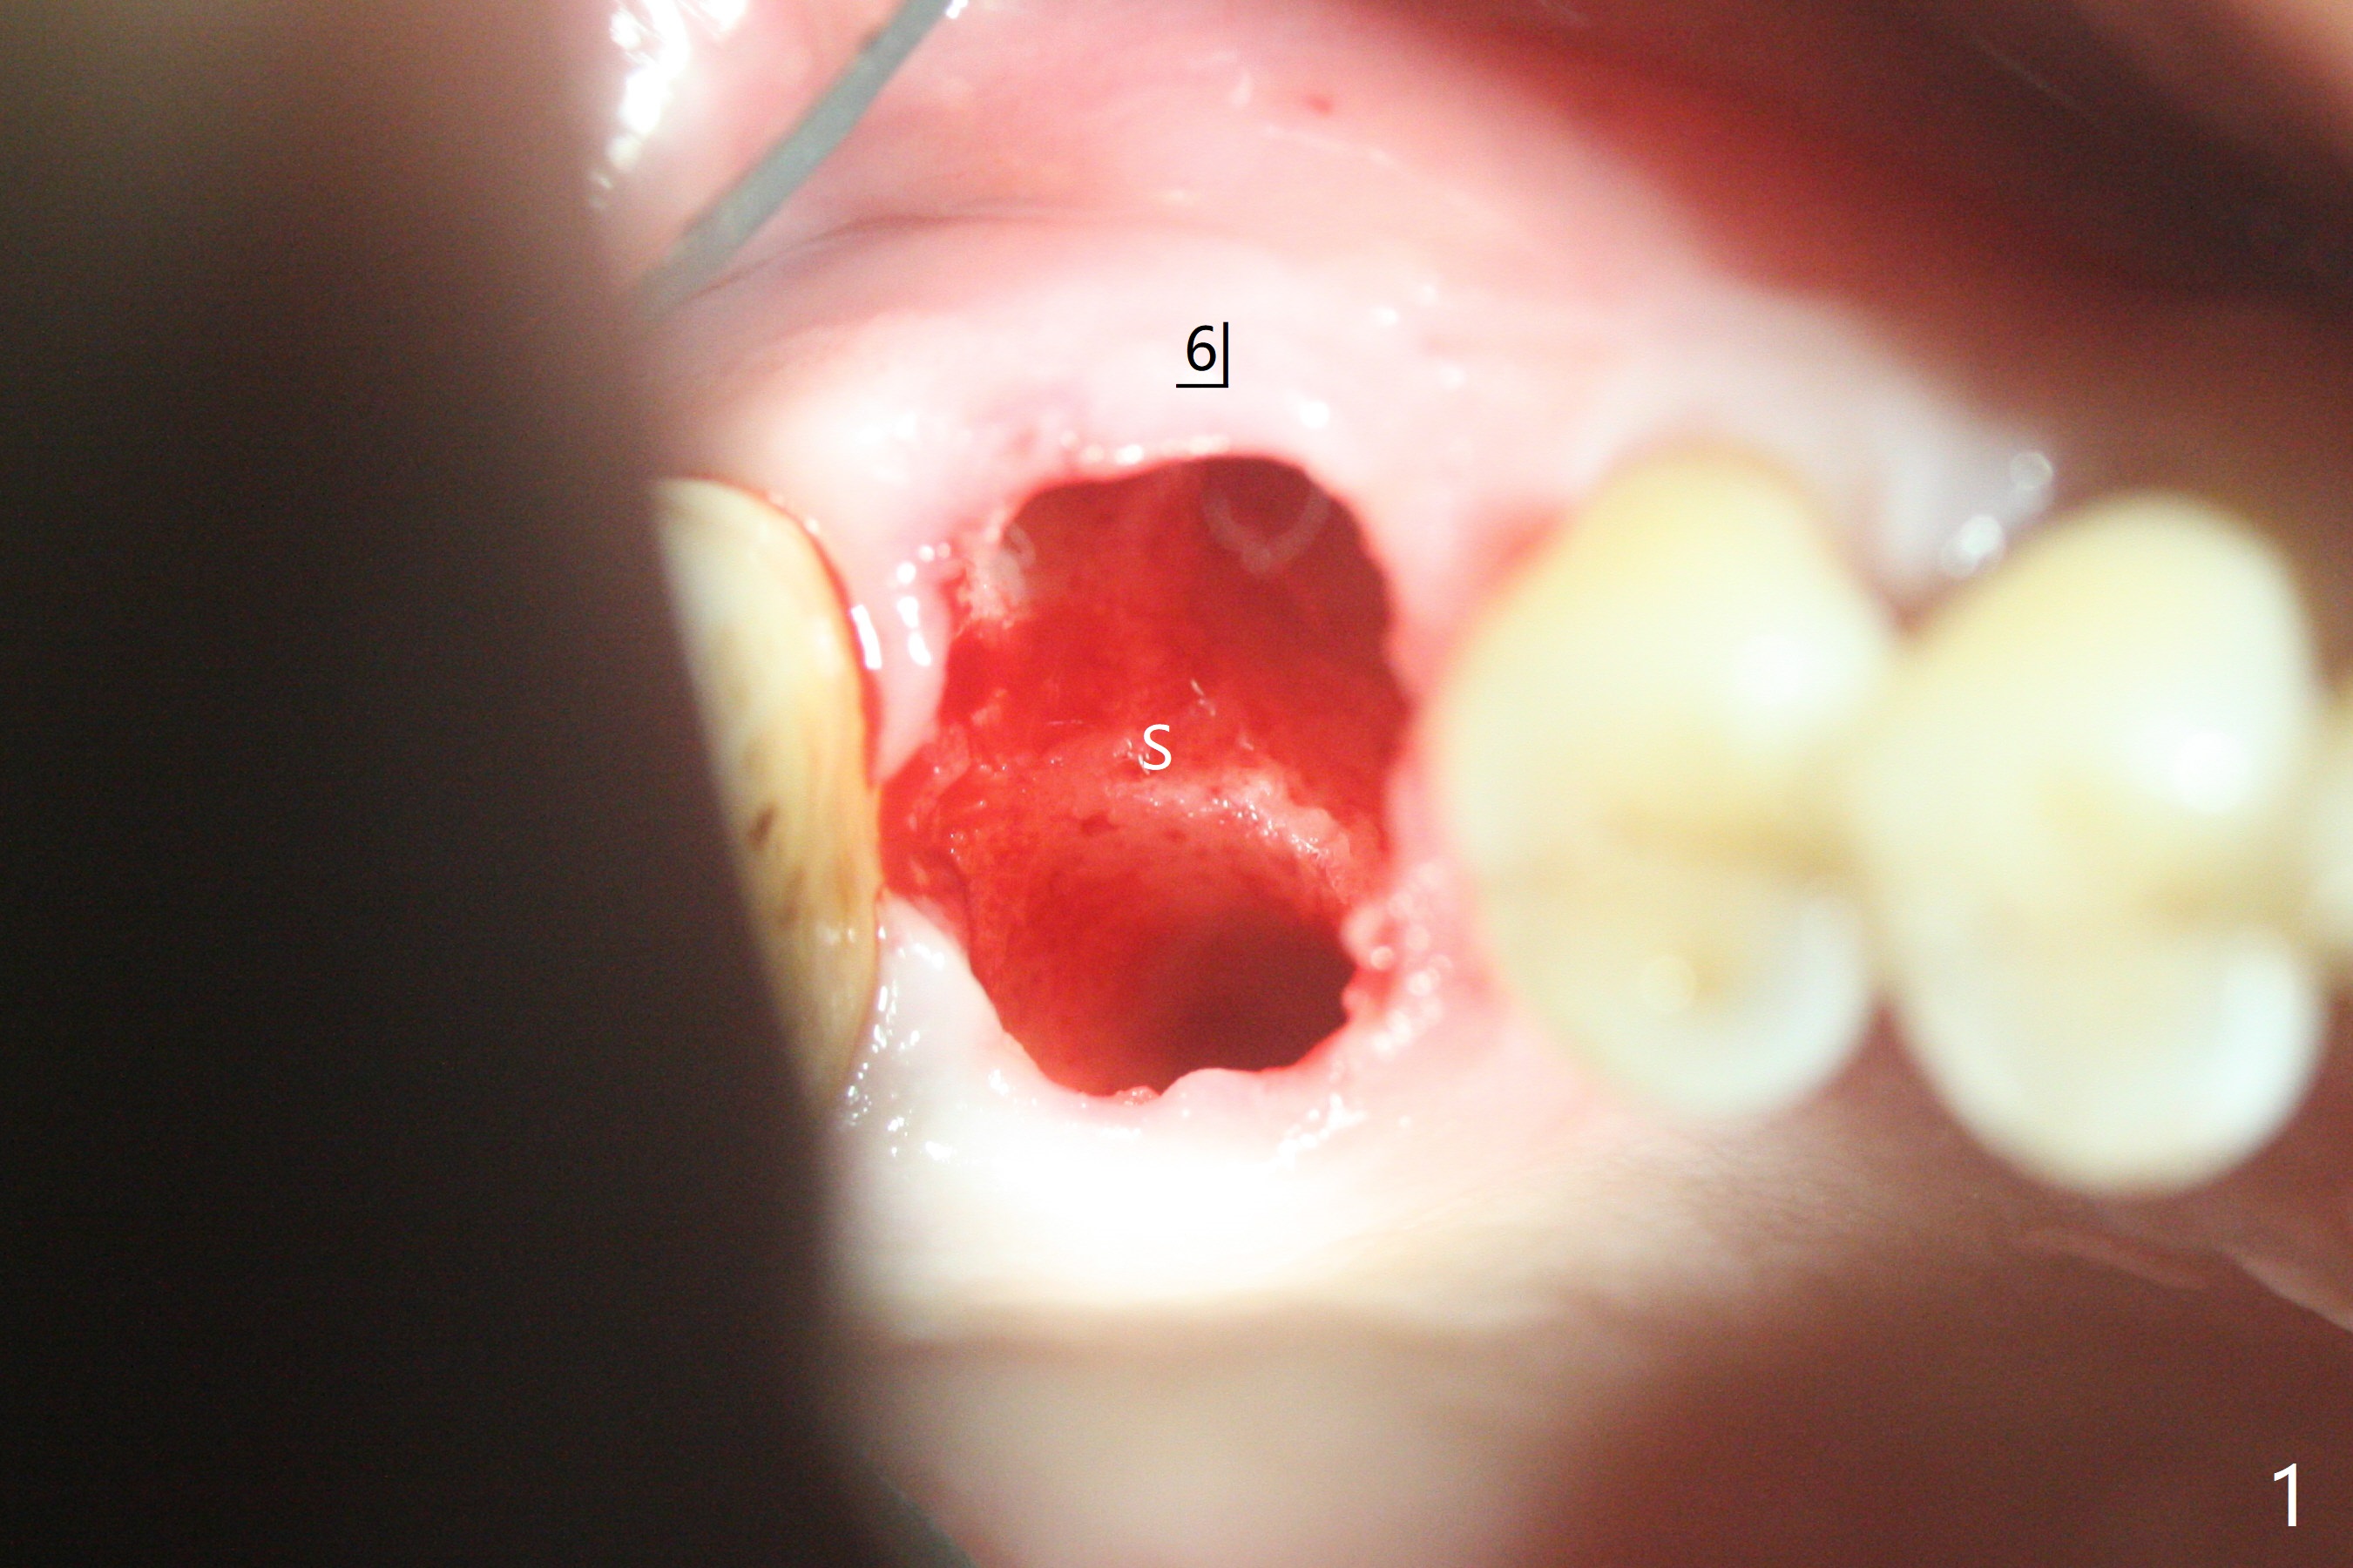

60岁男以前就害怕牙科治疗,一年前做一侧肾上腺切除,现在更紧张,不过挺配合。右上6手机切断拔除,虽然近中颊侧牙槽窝破坏厉害,中隔还很大(图一:S),利用导板顺利完成钻洞和提升术(图二:*)。植入正式植体后,放置第一轮粘性骨粉,至植体水平(确保植体深部周围没有缺失)而不影响基台置入,近中有不足之处(图三:*),第二轮骨粉补充(图四),最后覆盖PRF膜,临时牙冠固定。The crown/abutment/implant are found to have mild mobility 4.5 months postop, as related to #19 infection. A healing screw is placed. One month later, the wound heals; the bone density in the sinus increases (Fig.5 *), while that coronal to the implant decreases (^).愈合帽放置4个月,伤口还没有完全愈合,翻瓣后发现远中螺纹表面肉芽组织覆盖,去除后者,第一螺纹暴露。放置愈合基台后,从颊侧往远中缺陷填入骨粉(图六:*),缝合,覆盖树脂敷料。